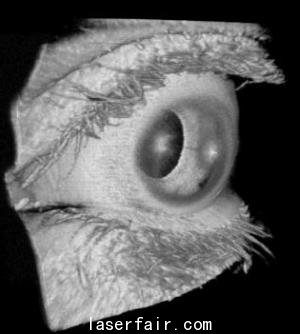

實(shí)際的例子很多,比如眼科。1.2 MHz的A-掃描速率可以在病人眨眼或者不由自主地移動(dòng)眼睛之前就可以完成對(duì)視網(wǎng)膜的大范圍掃描。另一個(gè)實(shí)例就是癌癥研究,使用微型OCT探針,可以1 MHz的A-掃描速率完成兔食管、結(jié)腸和胃的成像。這意味著,該技術(shù)在使用這種可調(diào)諧VCSEL實(shí)現(xiàn)人體內(nèi)窺鏡癌癥成像的應(yīng)用領(lǐng)域取得了進(jìn)步。

Potsaid說:“已經(jīng)證實(shí),在眼科成像中,這種VCSEL可以580 kHz的A-掃描速率、83 nm的波長(zhǎng)調(diào)諧范圍及8.9 μm的軸向分辨率對(duì)視網(wǎng)膜進(jìn)行掃描,提供適合視網(wǎng)膜成像的成像范圍。掃描前眼需要更長(zhǎng)的成像范圍,但是,通過降低VCSEL的掃描速率,同時(shí)保證相同的光譜掃描范圍,則可以在犧牲分辨率的情況下實(shí)現(xiàn)前眼掃描。”

在對(duì)眼睛的整個(gè)長(zhǎng)度進(jìn)行成像方面,可以更進(jìn)一步將VCSEL的掃描速率降到50 kHz,波長(zhǎng)調(diào)節(jié)范圍減小到45 nm。這樣做,分辨率略有下降,但成像范圍足以包括眼睛的整個(gè)長(zhǎng)度,從眼角膜到視網(wǎng)膜。